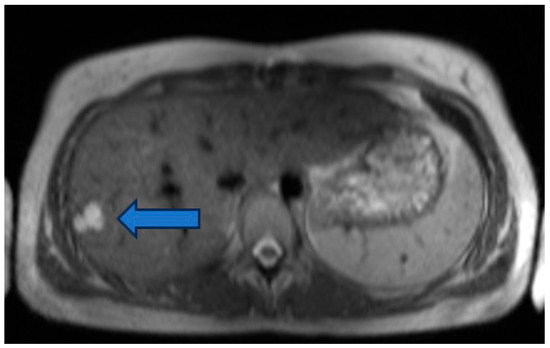

Incidental Hepatic Findings in Cardiac Magnetic Resonance Imaging Examinations in Patients with Congenital Heart Disease: A Pilot Study

Objectives: During cardiac magnetic resonance imaging (cMRI) exams in patients with congenital heart disease (CHD), incidental liver abnormalities are increasingly found. However, no systematic data exist on the incidence of liver lesions in patients with different CHDs. In order to gain a first overview, we retrospectively analyzed cMRI examinations from the last 10 years at our institution. Methods: CMRI examinations including T2-weighted images covering parts of the liver were performed on 899 patients with CHD at our institution between 2014 and 2024. The cMRI examinations were analyzed by a medical student, a pediatrician, a radiologist, and a pediatric cardiologist. Liver lesions were defined as atypical liver parenchyma, showing T2 hyper- or hypointensity compared to the surrounding liver tissue. Results: Liver lesions were found in 9.5% (85/899) of all cMRI studies; of these, 89% ((76/85) of cases) were unknown at time of cMRI, 96% (82/85) were T2 hyperintense, and 38% (32/85) were larger than 1 cm. The patients with liver lesions were older (29 years vs. 22 years, p < 0.0001). There were no sex differences in the incidence of liver lesions or differences in right or left ventricular function (LVEF: 57% vs. 58%, p = 0.78; RVEF: 55% vs. 54%, p = 0.35). The patients with univentricular hearts, transposition of great arteries after atrial switch operation, and atrial septal defects showed the highest incidence (18%, 17%, and 21%, respectively). However, 9% of patients with left heart-sided valve disease also showed liver lesions. Conclusions: Incidental findings of liver lesions in cMRI examinations of patients with CHD are reasonably high with almost 10%. In the growing population of adults with CHD, liver monitoring might be helpful to assure overall patient health. Full article

Figure 1